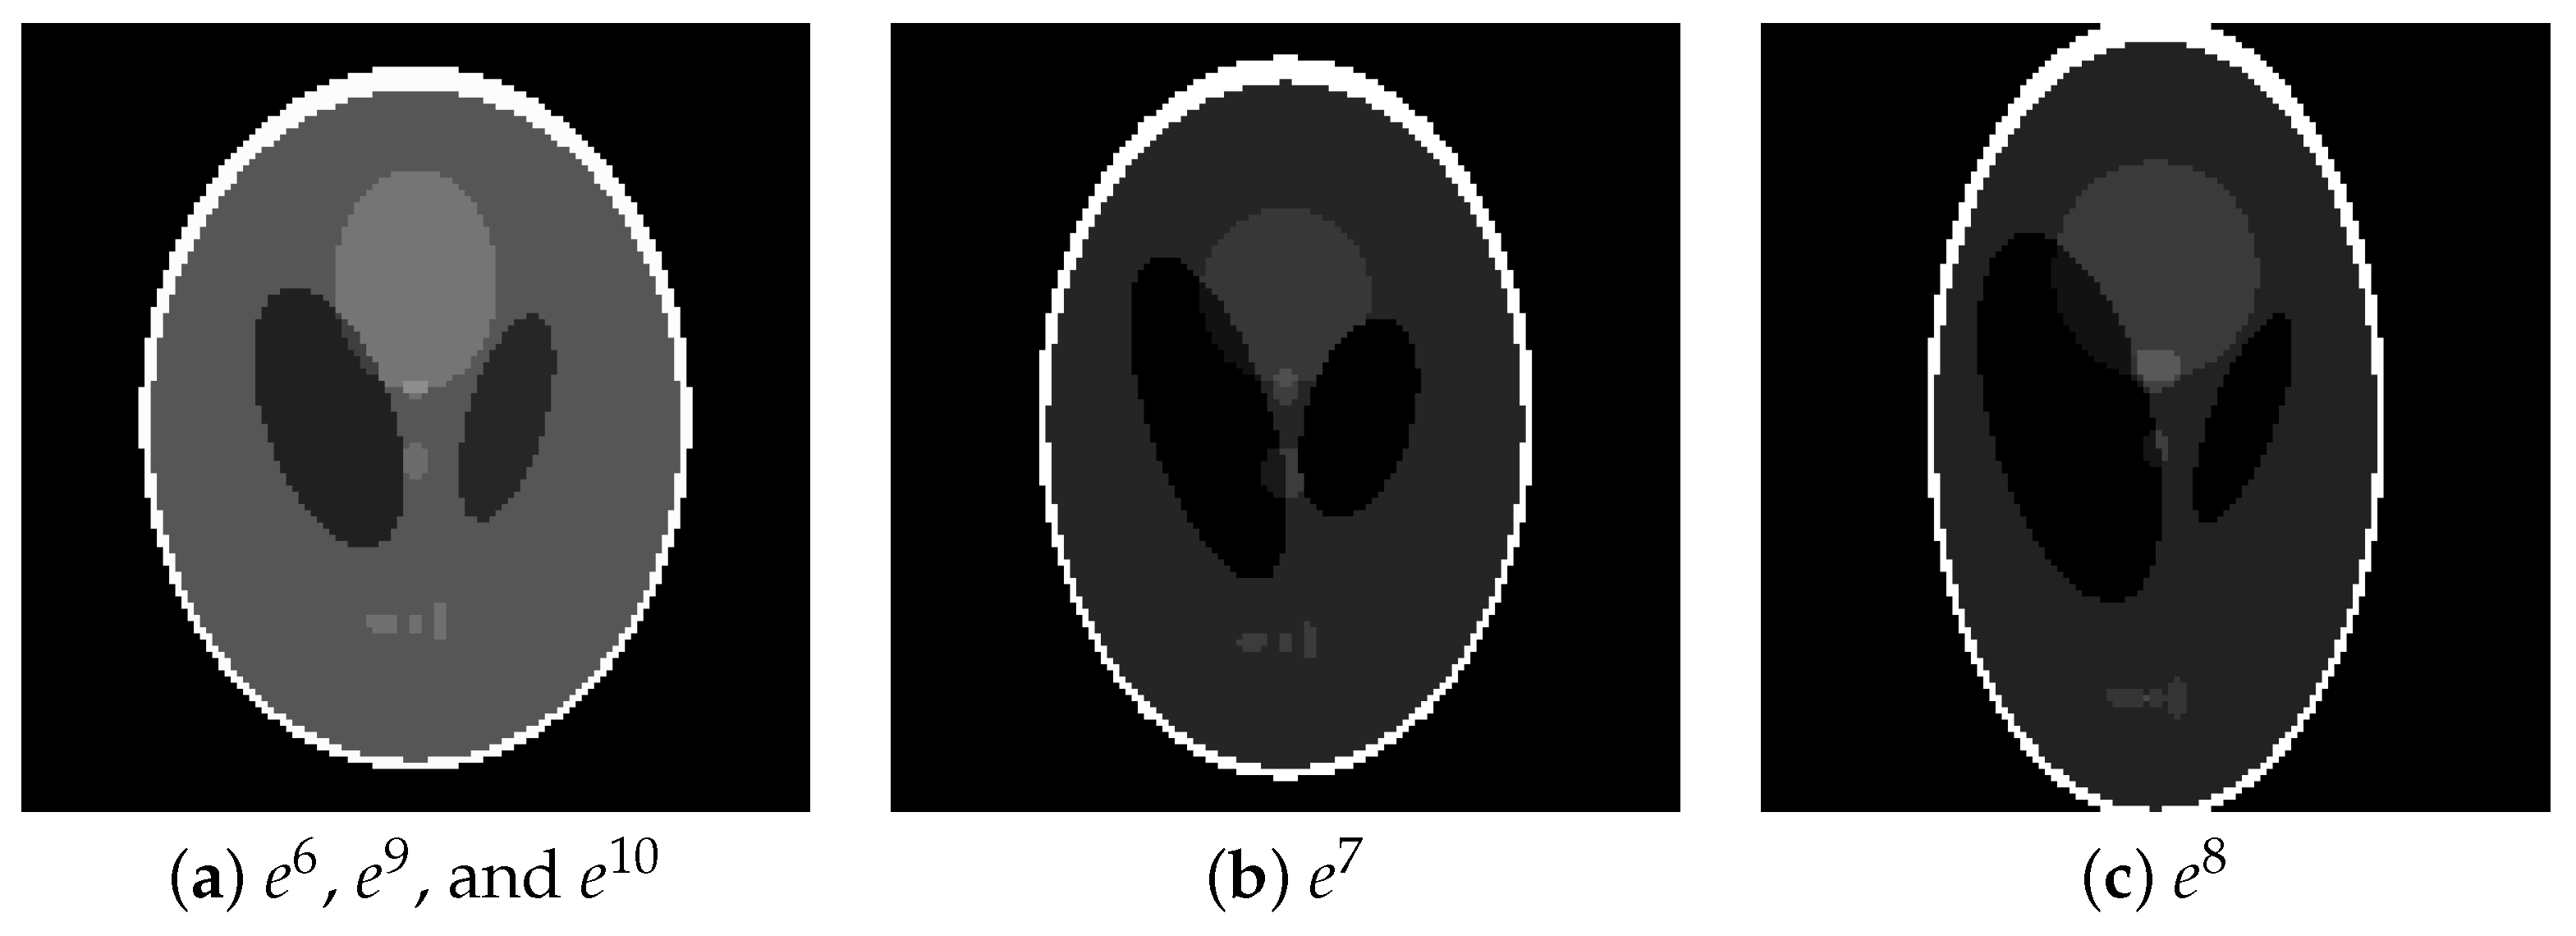

We generated projections , which were magnified versions of projections . These projections were generated from phantoms shown in Figure 12, which were enlargements of . The projection noise level to be applied was the same as in the previous subsection. The number of projection directions was increased to 180 so that the inverse problem would not be unduly difficult due to the large image size . In the proposed use case, the parameters are estimated on the basis of a smaller projection reduced from the larger projection, but here the procedure is inverted. That is, the image reconstruction of projection for any uses the parameter estimated from its smaller version, projection .

Figure 12.

Phantom images of (a) , , and , (b) , and (c) for testing.

Figure 13 plots the values of the evaluation function during reconstruction. The same trend as in Figure 10 is obtained when the parameters estimated from the reduced projection are diverted. The contour maps of the parameters shown in Figure 14 are also consistent with the trend in Figure 11, suggesting that it is possible to use the parameters estimated from the miniaturized projection. Although developing a method to reduce the size of the large original projection appropriately is required for actual use, the results show the possibility of a practical application.